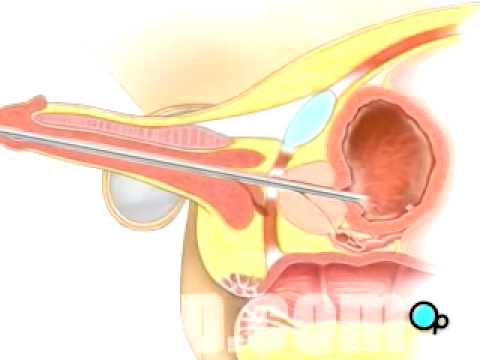

Urethral intercourse or coitus per urethram is sexual penetration of the female urethra by an object such as a penis or a finger. It is not the same thing as urethral sounding, the act of inserting a specialized medical tool into the urethra as a form of sexual or fetishistic activity.

Urethral intercourse or coitus per urethram is sexual penetration of the female urethra by an object such as a penis or a finger. It is not the same thing as urethral sounding, the act of inserting a specialized medical tool into the urethra as a form of sexual or fetishistic activity.

Urethral intercourse. Urethral intercourse or coitus per urethram is sexual penetration of the female urethra by an object such as a penis or a finger. It is not the same thing as urethral sounding, the act of inserting a specialized medical tool into the urethra as a form of sexual or fetishistic activity.

It is not the same thing as urethral sounding, the act of inserting a specialized medical tool into the urethra as a form of sexual or fetishistic activity. The untrained insertion of foreign bodies into the urethra carries a significant risk that subsequent medical attention may be required.